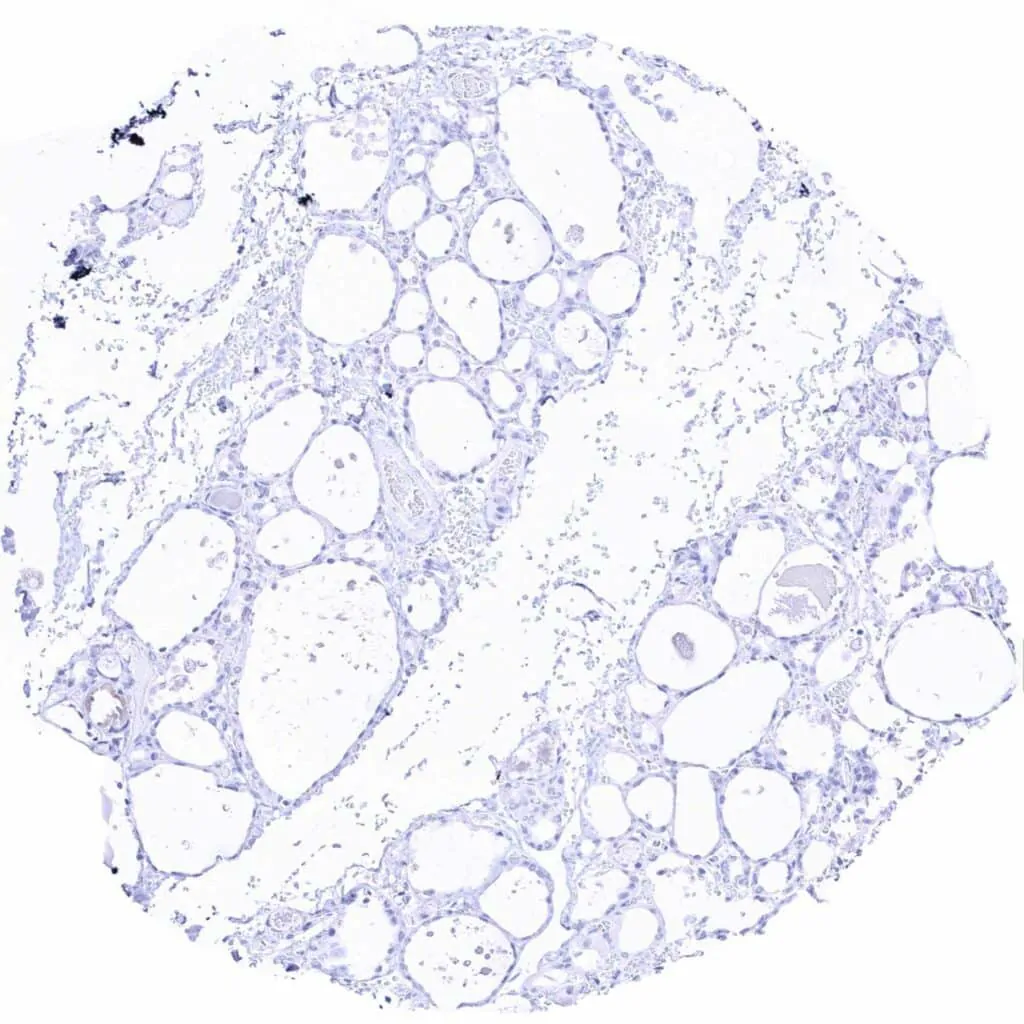

Ovary, follicular cyst – CD38 staining of some inflammatory cells

Ovary, stroma